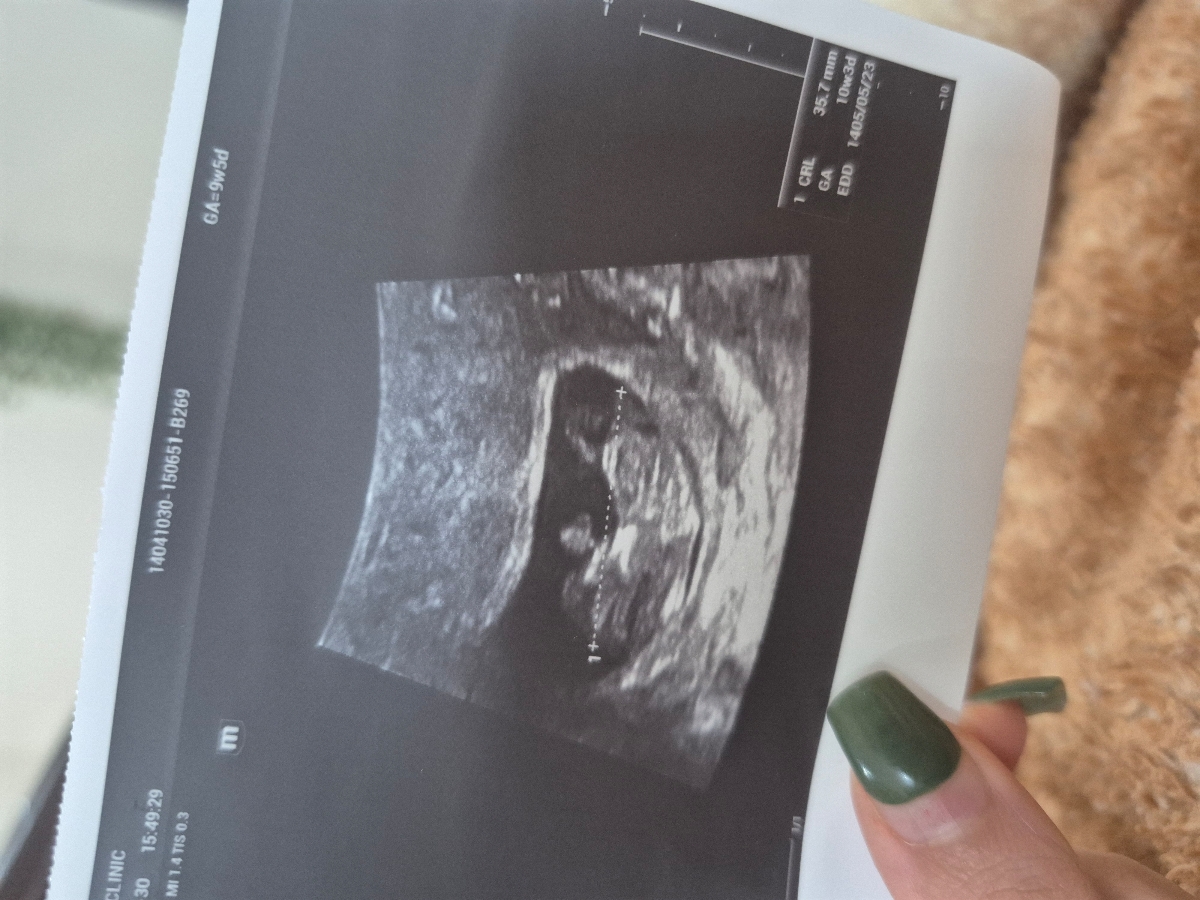

من هفته پیش برای سونو اقدام کردم و این تصویری که میذارم ماله سونوگرافی هست من ۹ هفته و ۵ روز بودم رفتم

اما تو سونو اعلام کردن سن جنین ۱۰ هفته و سه روز هست

الان داشتم راجب سونوnt تحقیق میکردم راجب تصویر جنین سالم و غیر سالم مطالبی بود که نباید پشت گردن جنین ضخیم باشه من خیلی استرس گرفتم بنظرتون تو عکس سونو من مشکلی هست؟

اخه تو این تصویر پشت گردنش خیلی ضخیمه

اما الان این تصویر یکم نگرانم کرده از بابت سونو nt

وقت سونو nt هم هفته آینده هست

جانم از روی عکس که تشخیص نمیگذاریم در سونوگرافی ان تی ضخامت دقیق در موقعیت های خاص چک میشود اگر به تشخیص با عکس بود که دیگر نیازی نبود همکاران سونولوژیست برای انجام nt دوره های بسیار تخصصی ببینند همه همکاران این سونوگرافی را انجام میدادند این عکس ها سایه و کنتراست دارد